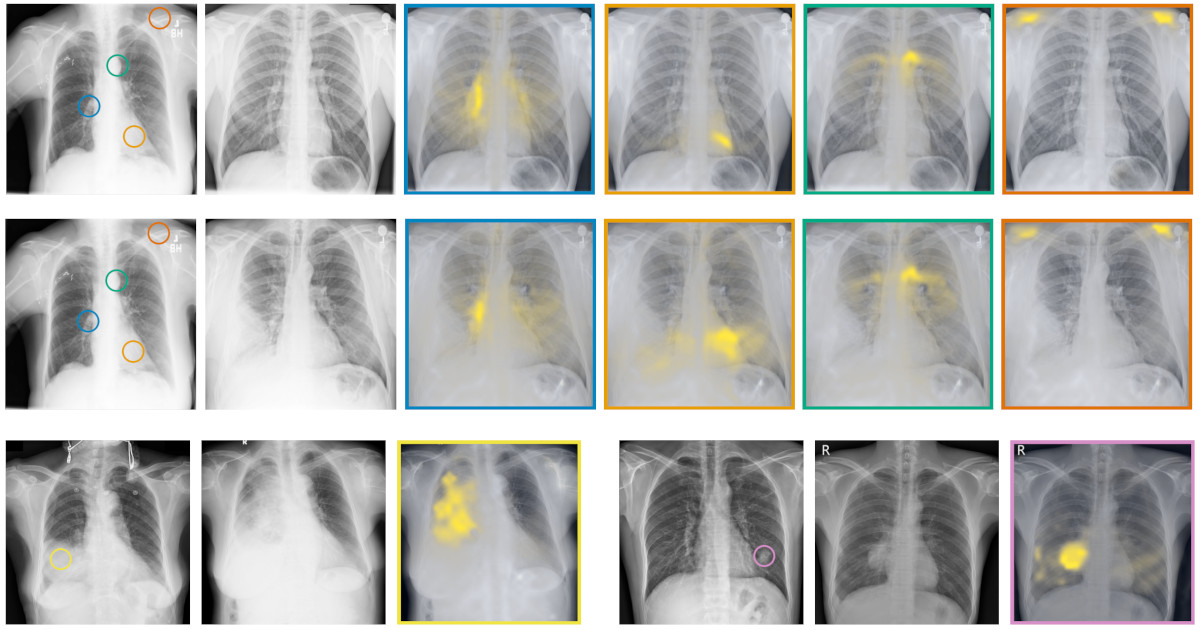

RadEdit: stress-testing biomedical vision models via diffusion image editing

F. Pérez-García, S. Bond-Taylor, P.P Sanchez, B. van Breugel, D.C. Castro, H. Sharma, V. Salvatelli, M.T. Wetscherek, H. Richardson, M.P. Lungren, A. Nori, J. Alvarez-Valle, O. Oktay, M. Ilse